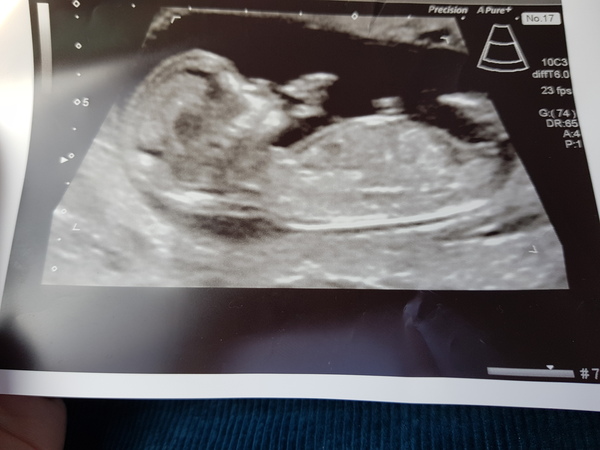

Finally went for my scan today :) baby was really active Smile. They previously estimated me at 12 +1 but after the scan they are sayig 13 week. All is looking good though, will attach my scan picture. Feel free to guess the gender 🤣

@Mummy0fboys what a lovely clear pic!